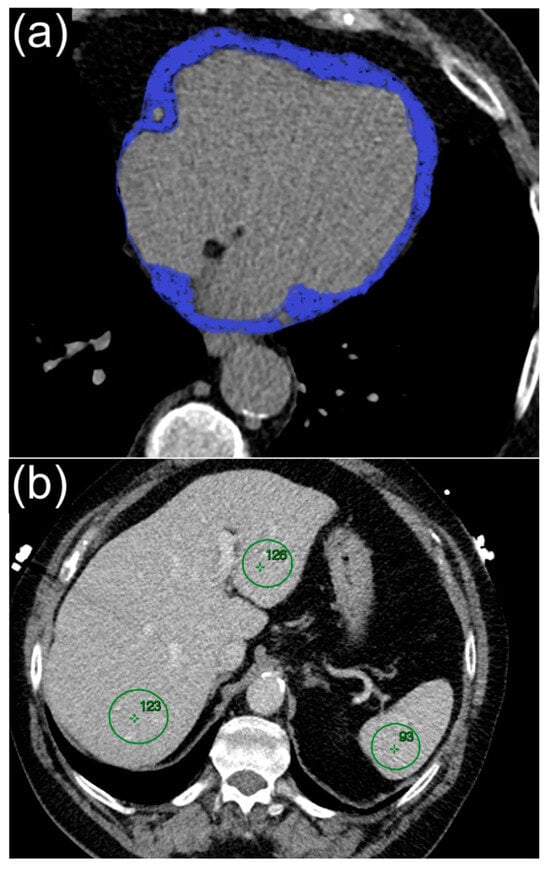

2.4. Liver Fat Measurement